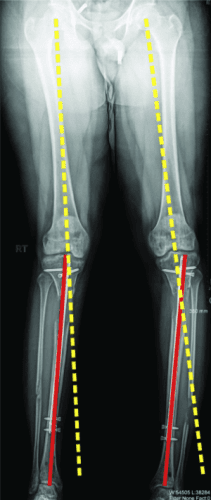

8 轴向偏差

继发于延长的轴向偏差或畸形并不是一个罕见的问题。它通常是可以预防的。使用转子钉更有可能出现内翻畸形。出于这个原因,我更喜欢使用梨状肌入口钉。在股骨近端延长术中,如果截骨术是在骨头紧贴指甲周围的地方进行的,则内翻成角的可能性不大。如果需要进行更近端的股骨截骨术,内侧阻断螺钉可以防止内翻偏斜。

轴向偏斜是胫骨中更常见的问题。胫骨往往会延长成外翻和外翘。为防止这种情况,钉子应插入正确的起点,该起点非常高,并且尽可能靠后,在胫骨的外侧,并在额平面的膝盖中心。如果指甲与截骨术上方的外侧皮层之间有空间,则应在该空间中插入阻挡螺钉。如果指甲与后皮层之间有空间,则在那里插入另一个阻挡螺钉。我设计了 STRYDE 钉子,通过提供第三个近端锁定螺钉(P2.2 只有两个)来抵抗轴向偏差。如果遵循所有这些预防措施,则不会随着延长而出现屈曲或外翻畸形。

敲击(外翻)鞠躬(内翻)

屈曲(procurvatum)

在外部机构胫骨身材延长并出现双侧并发症的患者。他发展了胫骨和 Abu/a 延迟结合,右侧是敲击 {外翻),左侧是弓形 {内翻),两侧是 f1exion {procurvatum}。我们在手术室使用临时外部斧头机对两侧进行了急性矫正,并放置了新的胫骨杆。我们在 Abu/a 延迟结合上放置了逆行杆。